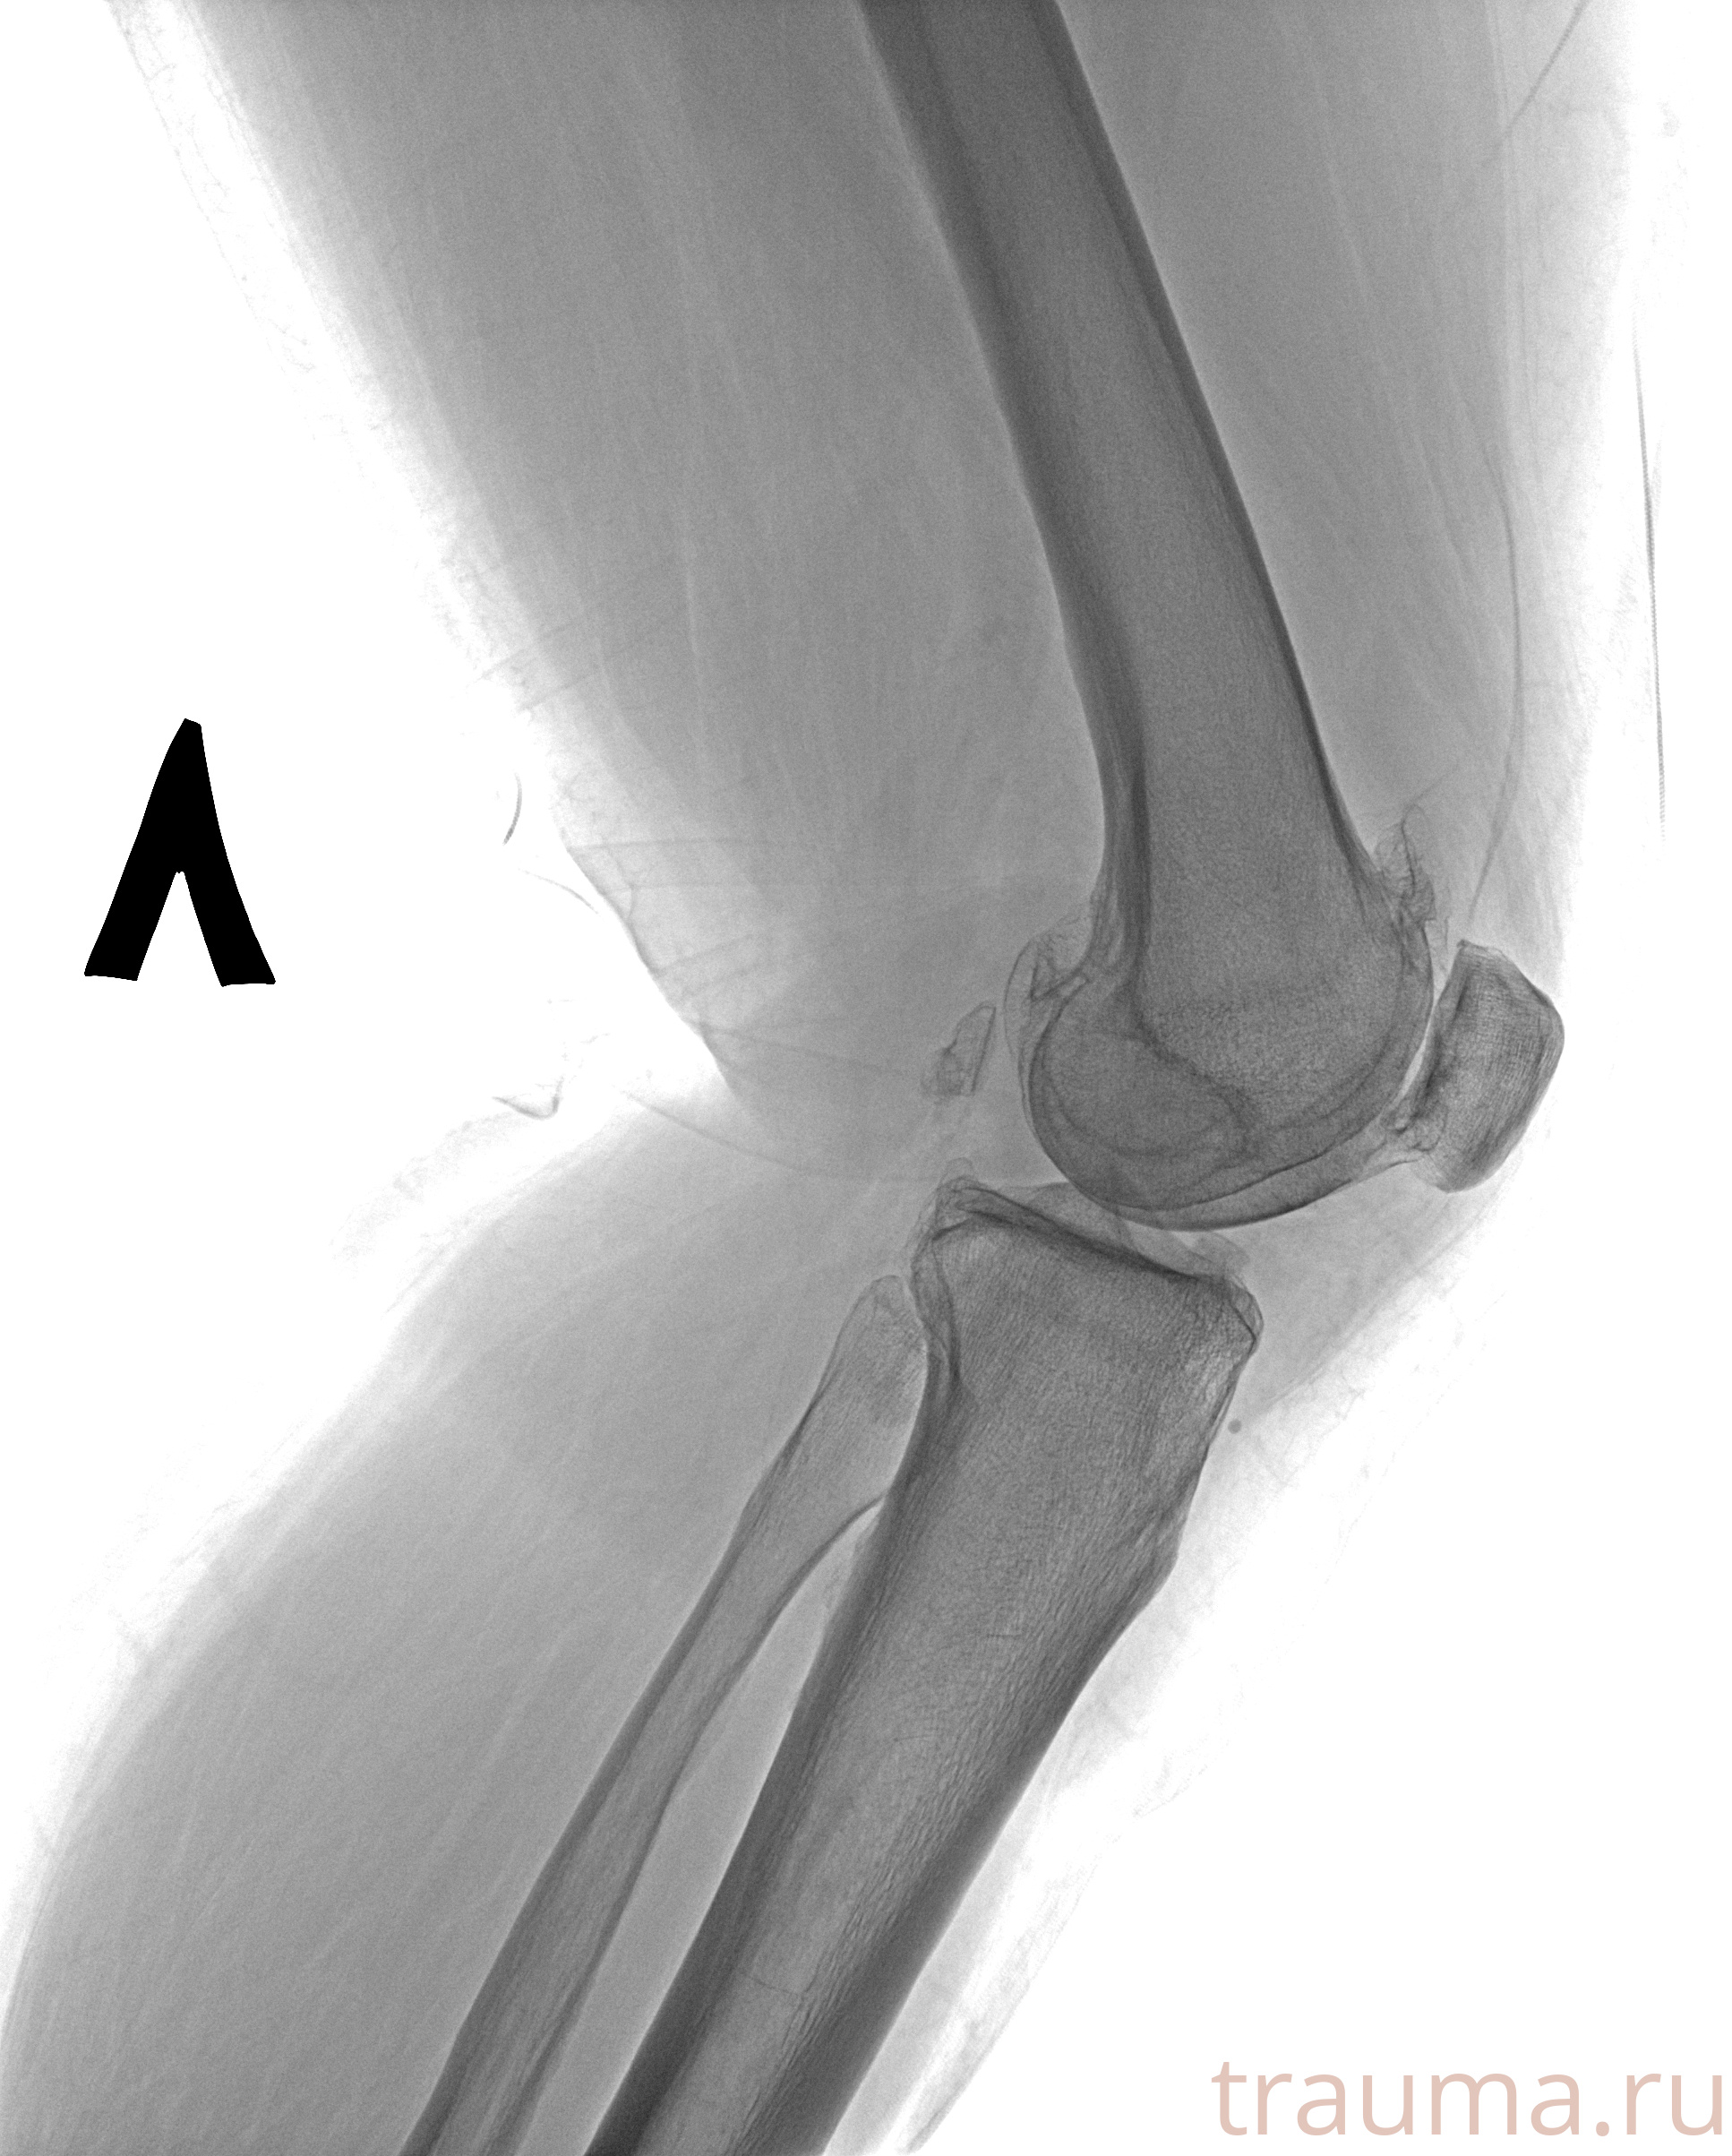

Рентген на дому: по вашему адресу приезжает врач-рентгенолог, травматолог-ортопед с мобильным рентгеновским аппаратом, проводит диагностику травмы или заболевания, делает необходимые рентгенограммы, дает рекомендации по дальнейшему лечению. Получить качественные снимки в домашних условиях возможно благодаря уникальной методике, разработанной МосРентген Центром для института  Склифосовского